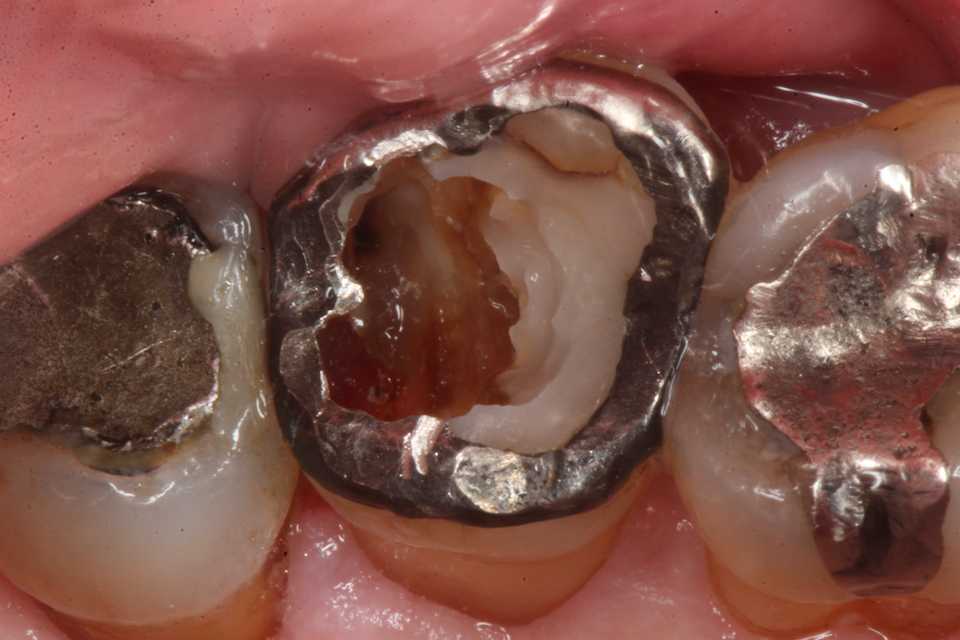

補強冠を入れて崩壊を防いでいたが、とうとう遠心隣接面が崩壊した。切削バーもスプーンエキスカベータも届きにくいし、歯肉側のエナメル質も失われていて、象牙質も軟化象牙質に近くなっている。

通常治療では神経を取ってクラウンを被せるということになるのだが、治療困難な1番奥の歯では頑張っても上手く行く可能性は低い。患者も何度も通わせられた結果、歯の寿命は短くなるだけだ。

結局、抜歯とインプラントを勧められる事になる。しかし咬合力が強いとインプラントの対合歯が傷むことになり負の連鎖は続くので、外傷性咬合のある方はインプラントは禁忌になっている。

今回の実際の治療法はマージン付近の1mm幅だけは接着シロの為の健全歯質を確保し、露髄しない程度に軟化象牙質を除去し、3MIX+α-TCPで覆罩し、歯質の再硬化を期待するしかない。